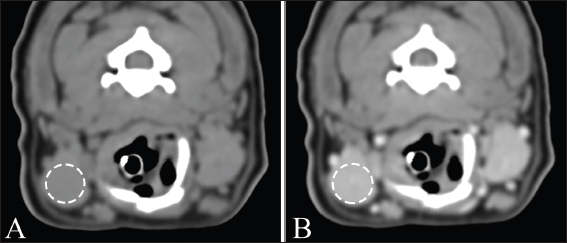

The maximum cross-sectional area (MCSA) of the bilateral mandibular and zygomatic glands was measured on non-contrast transverse CT images (Fig. 1). The region of interest (ROI) for MCSA was manually drawn including the largest area of the salivary glands. The attenuation was measured by drawing a circular ROI in each salivary gland on non-and postcontrast transverse images in all dogs (Fig. 2). The ROI was drawn as large as the anatomic configuration within each salivary gland, with the exception of obvious vascular areas. This ROI was created thrice in each salivary gland, and the attenuation value was defined as the mean of the three values. All measurements were performed by one author with 2 years of experience in veterinary diagnostic imaging, with consultation with another author with 15 years of experience in veterinary diagnostic imaging.

Fig. 1. Measurement of MCSA of bilateral mandibular glands (A) and zygomatic glands (B). Outlines of each salivary gland (dotted line) are drawn manually on CT images.